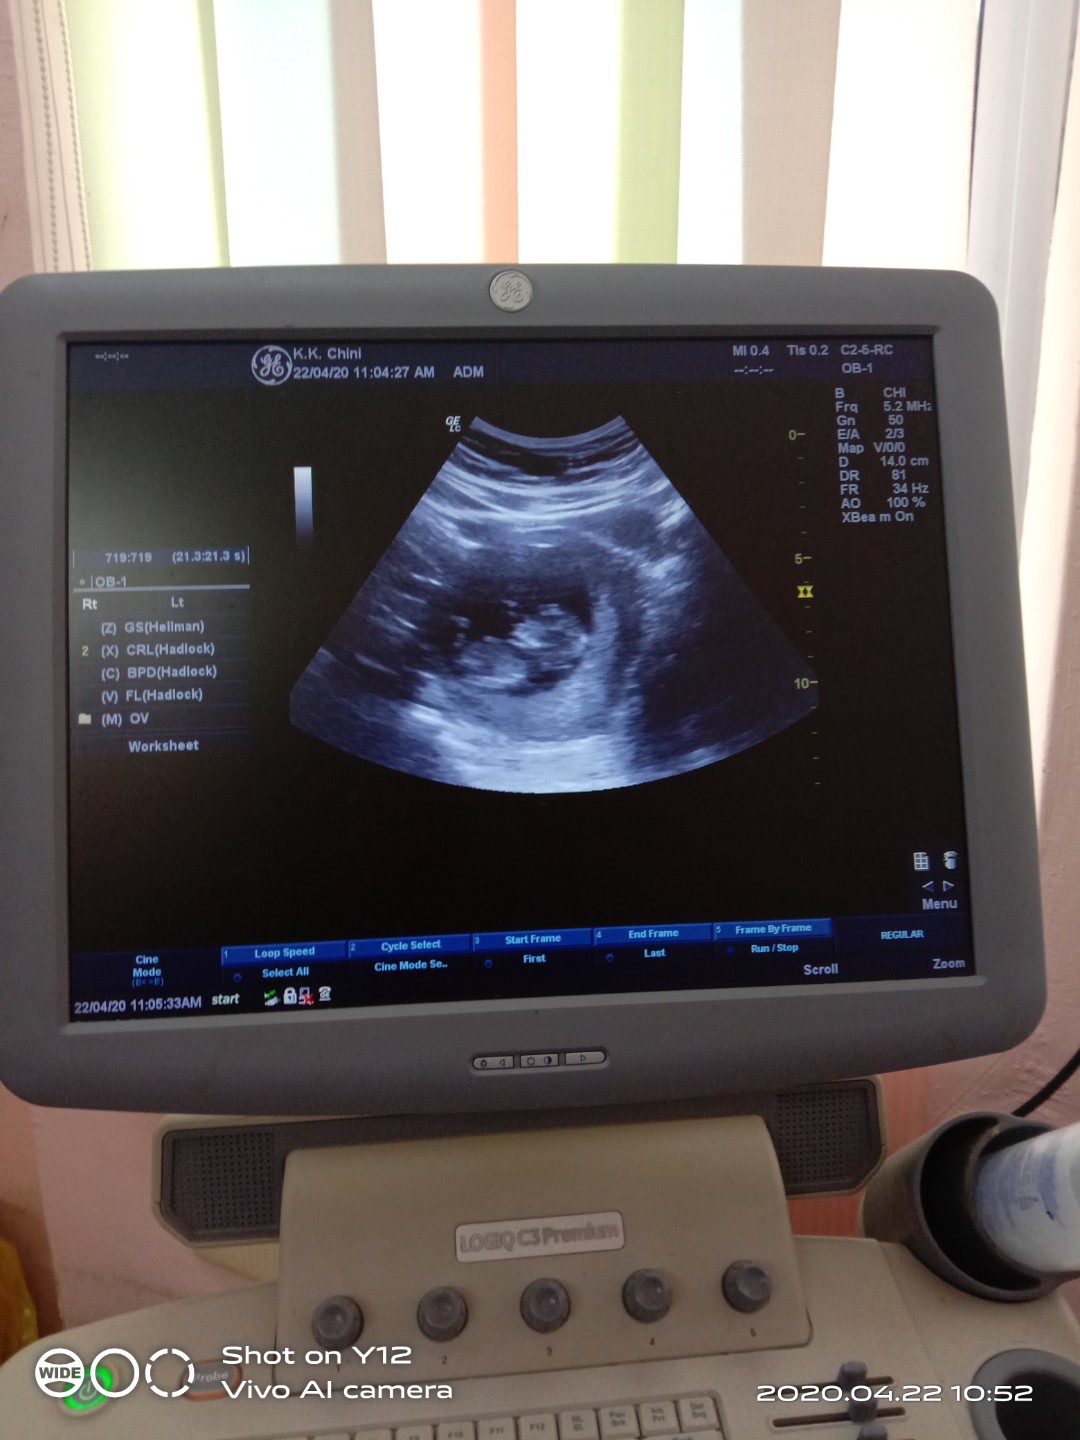

Saya 10 week nmpk kantung je .. ni scann blk 13 week tetiba dh besar .. ee comel je ..

Normal, saya scan last week pun 6 mggu nampak kantung je. Doc kata lagi 2 mggu scan lagi skli😊